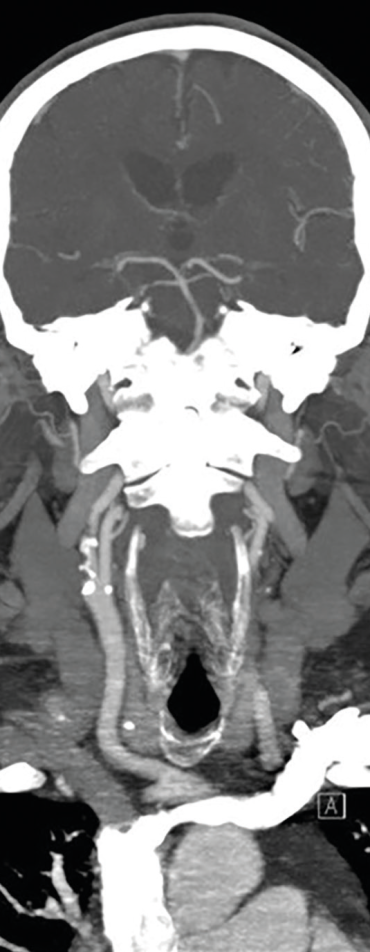

Obr. 2 CT angiografie extrakraniálních a intrakraniálních tepen s významnou kalcifikovanou stenózou pravé ACI ACI – arteria carotis internaMuž, 69 let, dlouholetý kuřák, byl přijat na naše neurologické oddělení pro druhou ataku amaurosis fugax vpravo v průběhu pěti dnů. Přechodnou slepotu popisoval jako náhle vzniklý stav, při kterém měl pocit, že se mu velmi rychle vytvořila clona před pravým okem. Obě ataky prchavé monokulární amaurózy netrvaly déle než 2–3 minuty. Po druhé atace vyhledal očního lékaře, který provedl komplexní oftalmologické vyšetření včetně očního pozadí, optické koherentní tomografie a zorného pole. Nález na předním segmentu oka byl oboustranně přiměřený věku. Na očním pozadí dominovaly změny chronické hypertonické retinopatie. Zorné pole bylo v pořádku. Při přijetí na neurologické oddělení byl neurotopický nález v normě. Dle anamnézy se měl pacient léčit pro arteriální hypertenzi a hyperlipidemii, ale léky přestal užívat, protože se cítil zdráv. Při vstupním měření krevního tlaku byly zjištěny hodnoty 200/100 mm Hg. Akce srdeční byla pravidelná a vstupní elektrokardiografické vyšetření (EKG) doložilo sinusový rytmus. Fibrilace síní nebo jiná arytmie nebyly zachyceny ani při monitoraci EKG během hospitalizace na neurologické jednotce intenzivní péče (JIP). Glykemický profil byl v normě. Při vyšetření koncentrace lipidů v krvi byla zjištěna hypercholesterolemie s hodnotou LDL cholesterolu 2,94 mmol/l. Vyšetření mozku pomocí CT neprokázalo známky akutního krvácení či ischemie (obr. 1). Dle současně provedené CTA mozkových tepen byla zjištěna významná stenóza pravé ACI, nicméně hodnocení jejího stupně bylo modifikováno výraznějšími kalcifikacemi (obr. 2). Vzhledem k tomuto nálezu byla ke korelaci s CTA doplněna duplexní sonografie extrakraniálních tepen, která potvrdila 80–85% stenózu pravé ACI (obr. 3, 4). Dle transkraniální barevně kódované duplexní sonografie (TCCS) byly morfologie a hemodynamické poměry intrakraniální cirkulace v normě, nebyly zachyceny ani mikroembolické signály. V léčbě byly indikovány kyselina acetysalicylová 100 mg denně (nejprve podána nasycující dávka 300 mg) a CEA. Současně byly nasazeny atorvastatin v dávce 80 mg denně a inhibitor angiotenzin konvertujícího enzymu (ACE) v léčbě arteriální hypertenze.

Obr. 4 Symptomatická stenóza pravé ACI 80–85 % ACI – arteria carotis internaNeodkladně provedená klinická a zobrazovací vyšetření u pacientů s amaurosis fugax jsou zásadní pro zjištění její etiologie a nastavení sekundární prevence cerebrovaskulárních příhod. Důležité je vyšetření magistrálních mozkových tepen. Přítomnost symptomatické intrakraniální nebo extrakraniální okluze či stenózy > 50 % je podle studie CATCH nejvýznamnějším prediktorem jak pro recidivu amaurosis fugax nebo retinálního infarktu, tak především pro mozkový infarkt. Karotická endarterektomie je podle současných klinických doporučení zlatým standardem v léčbě symptomatické stenózy ACI. CEA je indikována u pacientů se 70–99% symptomatickou stenózou ACI, kterým přináší nejvýznamnější klinický přínos s absolutním snížením rizika iCMP o 16 % v průběhu následujících pěti let. Operace by měla být provedena optimálně během dvou týdnů od amaurosis fugax (2.–14. den). Čím dříve je CEA provedena, tím významnější je redukce rizika recidivy iCMP. Před provedením, v průběhu a po CEA by neměly být vysazeny ASA a statin. Věk není absolutní kontraindikací, z CEA profitují i pacienti starší 75 let, pokud nemají závažné srdeční či jiné limitující onemocnění. U pacientů se symptomatickou stenózou ACI 50–69 % může být CEA zvážena v případě, že bude provedena na pracovišti s nízkým rizikem perioperační morbidity a mortality (< 3 %), ale profit z výkonu je menší (absolutní redukce rizika o 4,6 %). Benefit CEA u pacientů s < 50% stenózou ACI nebyl prokázán.